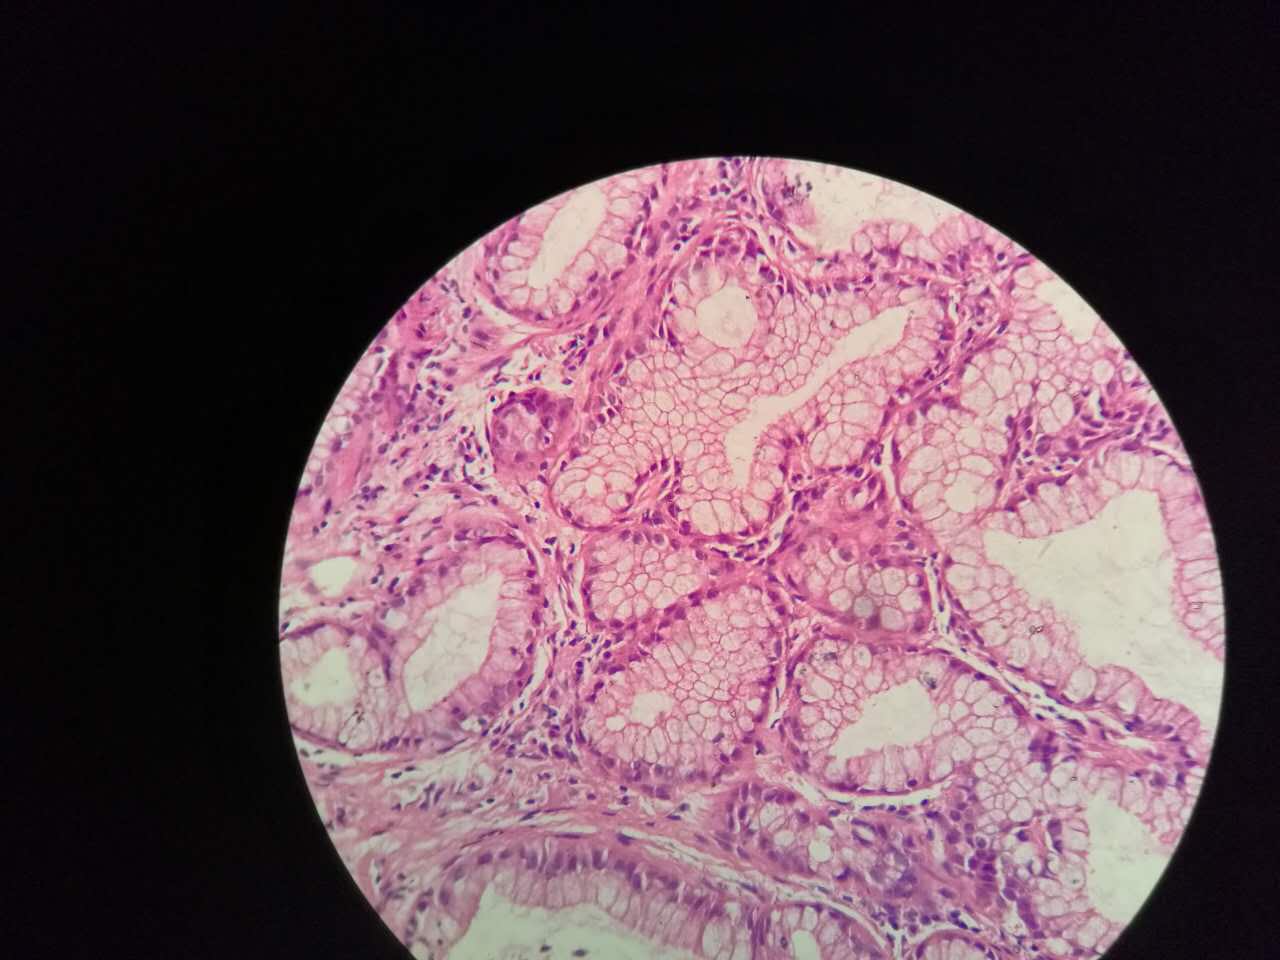

粘液型腺癌

粘液型腺癌是原发肺腺癌中的一种特殊类型

细胞内外含较多粘液

粘液型腺癌,细胞内粘液多,有点儿像支气管的粘液腺

单纯的粘液腺,没有浆液腺

粘液型腺癌的肿瘤细胞排列整齐,核位于基底,细胞呈柱状。

肺泡间隔(间质)经常比较细

差不多都长这样

这个生长密集,相对要重

这个细支气管,一半癌浸润

肿瘤细胞形态仍然相似

中央有个肺血管,说明破坏力不强